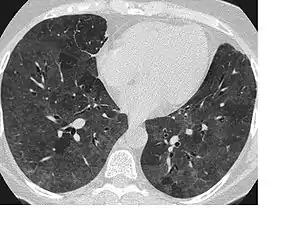

در رادیولوژی، نمای گراند گلاس یا کدورت شیشهٔ مات (به انگلیسی: Ground-glass opacity) یک یافتهٔ غیراختصاصی در سیتی اسکن است که به شکل یک کدورت مهآلود خود را نشان میدهد و ساختارهای زیرین خود، برونشها و عروق ریوی، را نامشخص نمیسازد. این نما نشاندهندهٔ پرشدگی قسمتی از فضاهای هوایی ریهها توسط اگزودا یا ترانسودا است، همچنین میتواند بهدنبال ضخیمشدگی بینابینی ریهها یا بر روی هم خوابیدن بخشی از کیسههای هوایی ریه نیز ایجاد گردد.[1] :95

تشخیص افتراقی نمای گراند گلاس شامل این موارد است: ورم ریوی، عفونتها (از جمله کروناویروس سندرم حاد تنفسی ۲،[2] سیتومگالوویروس و پنومونی پنوموسیسیتیس جیرووسی)، انواع بیماریهای غیر عفونی بینابینی ریه (مانند پنومونیت ازدیاد حساسیت، سندرم هامان-ریچ)، خونریزی آلوئولار منتشر و پنومونی سازمانیافته کریپتوژنیک.[3]